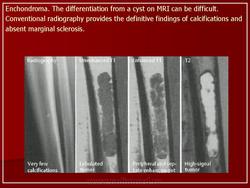

Хондрома. Это доброкачественная опухоль, развивающаяся из гиалинового хряща. Она может расти в полость костного мозга, и тогда называется энхондромой, или на поверхности кости, и тогда ее называют экхондромой, или поднадкостничной, юкстакортикальной хондромой. Энхондрома - наиболее частая разновидность внутрикостных хрящевых новообразований. Она встречается одинаково часто у лиц обоего пола, особенно на 3-м и 5-м десятилетиях жизни. Как правило, хондрома представляет собой одиночную опухоль, локализующуюся в метафизарных зонах трубчатых костей и чаще всего - в коротких трубчатых костях кистей и стоп. Синдром множественных энхондром - энхондроматоз - известен под названием болезни Оллье (L.Ollier), а в случае сочетания энхондроматоза с гемангиомой мягких тканей, заболевание называют синдромом Маффуччи (A.Mafflicci). Считают, что хондромы развиваются из остатков ростовых пластинок хряща, которые впоследствии пролиферируют и медленно увеличиваются. Поэтому неудивительно, что опухоли возникают в основном в тех костях, которые развиваются из зон энхондральной оссификации. Большинство энхондром отличается бессимптомным течением и обнаруживается случайно. Обычно они болезненны и приводят к патологическим переломам. При энхондроматозе хрящевые опухоли могут быть столь многочисленными и крупными, что вызывают серьезные деформации скелета. Рентгенологические признаки хондромы весьма характерны, так как неминерализованный узел хряща образует хорошо ограниченные, овальные участки просветления, окруженные тонким ободком рентгеноплотной кости. Если матрикс кальцифицируется, то это определяется по рентгеноконтрастной зоне, имеющей неправильные очертания. Хотя опухолевый узел делает эндост фестончатым, он не приводит к полному разрушению корковой зоны. Потенции к росту у хондром ограничены, поэтому многие опухоли долгое время находятся в стабильном состоянии. После удаления новообразования возможны рецидивы, особенно если опухолевый узел удален не полностью. Одиночная хондрома крайне редко подвергается малигнизации, которая чаще свойственна энхондроматозу. Кроме того, у больных с синдромом Маффуччи отмечается тенденция к развитию других опухолей, включая рак яичника и глиому головного мозга.

Как правило, хондрома в диаметре не превышает 3 см. Внешне это голубовато-серый полупрозрачный узел. Под микроскопом определяются четкие границы, развитый гиалиновый матрикс и умеренное или небольшое количество хондроцитов. Опухолевые хондроциты, располагающиеся в лакунах, выглядят вполне доброкачественными. По периферии узла хрящ подвергается энхондральной оссификации, а в центре опухоли он чаще всего обызвествляется и погибает. При синдромах Оллье и Маффуччи ткань хондромы может содержать много хондроцитов и иметь признаки клеточной атипии. В таком случае ее нелегко отличить от хондросаркомы.

Энхондроматоз.

https://radiopaedia.org/articles/enchondromatosis